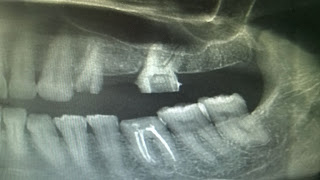

Before- Roadside Car Accident

After Treatment- Roadside Car Accident